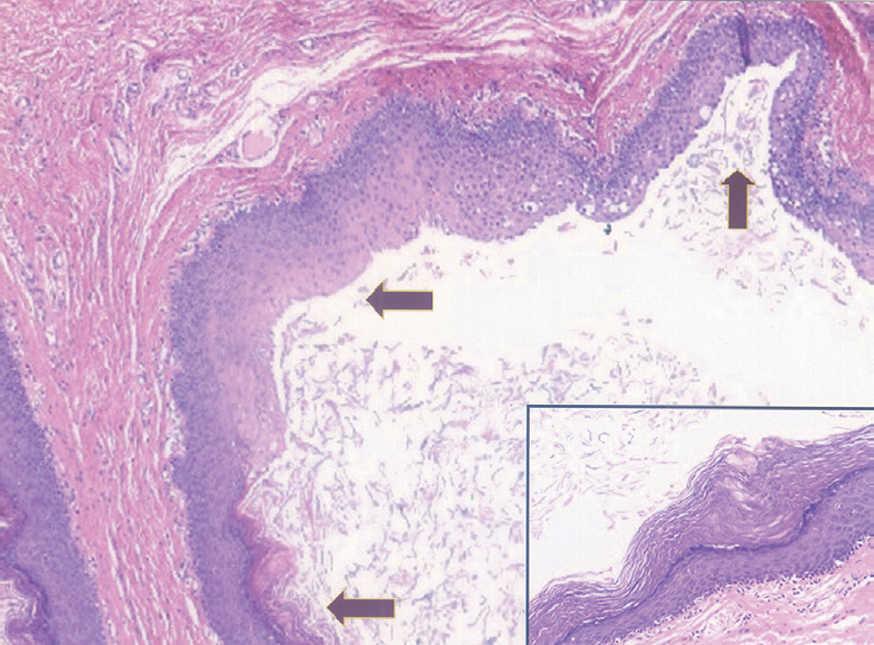

Fig. 3.--Área de diferenciación glandular con zonas de secreción por decapitación. (Hematoxilina-eosina, x200.)

El estudio histopatológico de una de las lesiones evidenció la presencia de una cavidad quística unilocular, localizada en la dermis profunda, sin conexión epidérmica. El epitelio de revestimiento de la cavidad estaba formado por una doble capa celular. Presentaba en algunas zonas distintos patrones de diferenciación, que se observaban en continuidad unos de otros (figs. 2 y 3).

La lesión quística se hallaba revestida por un epitelio escamoso estratificado con queratinización infundibular y, ocasionalmente, por un epitelio seudoestratificado de aspecto glandular, formado por células cilíndricas de citoplasma claro, proteínas amiloides séricas positivas, con imágenes ocasionales sugestivas de secreción por decapitación.

El estudio inmunohistoquímico reveló que en las áreas de diferenciación glandular las células del epitelio de revestimiento expresaban el antígeno epitelial de membrana (EMA), así como queratinas de bajo peso molecular (CAM 5,2), queratina 7 (K7) y el antígeno carcinoembrionario (CEA), y eran negativas para queratina 20 (K20). El epitelio escamoso era débilmente positivo para K7, y negativo para EMA, CAM 5,2, CEA y K20.